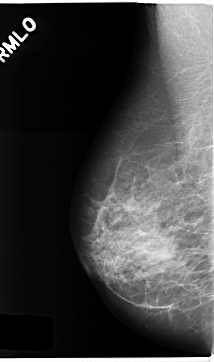

C_0239_1.LEFT_MLO

LEFT_MLO LINES 4728 PIXELS_PER_LINE 2696 BITS_PER_PIXEL 12 RESOLUTION 50 OVERLAY